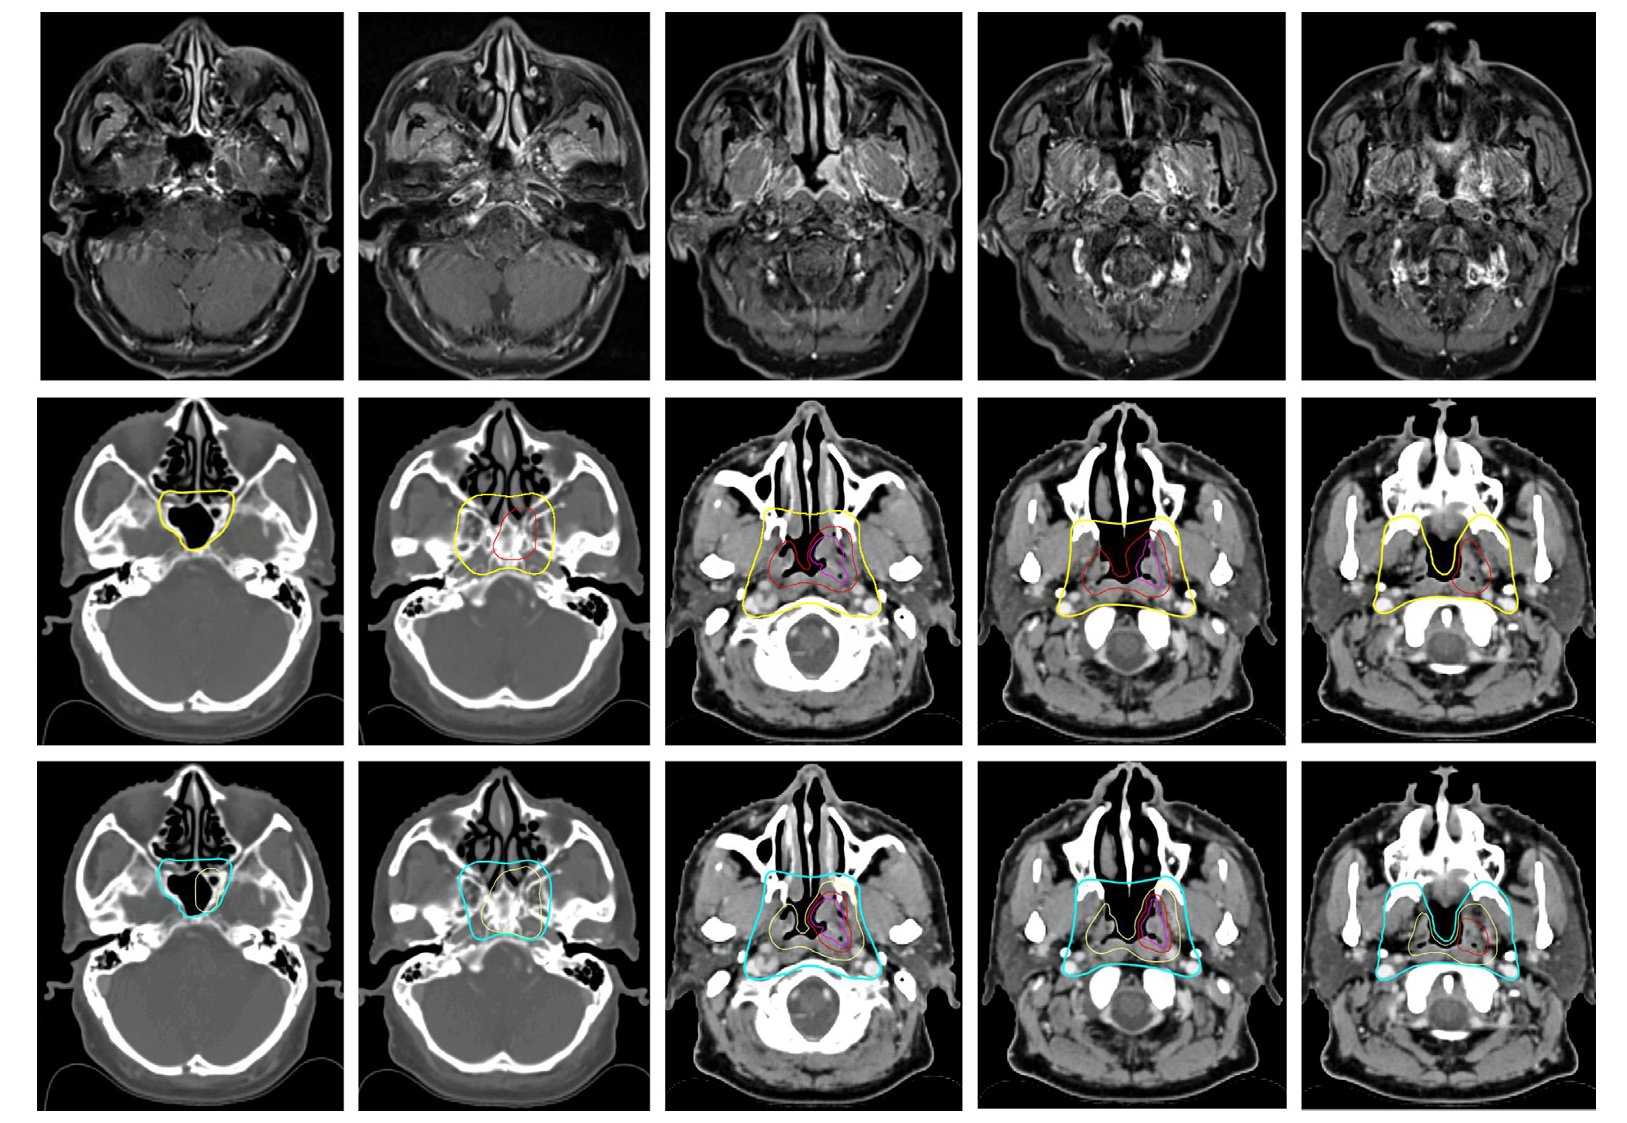

图2 淋巴结临床靶区的勾画

对于颈部淋巴结的靶区勾画,新指南同样进行了优化:

- 高危淋巴结靶区:对于无淋巴结外侵犯的患者,外放边界建议为0-5毫米;而对于有晚期淋巴结外侵犯的患者,则强烈推荐5-10毫米的外放边界,处方剂量为70 Gy。

- 可疑淋巴结:建议不设外放边界,处方剂量设定为60 Gy。

- 低危淋巴结靶区(选择性照射区域):处方剂量统一为50 Gy。指南明确了双侧咽后、II、III、Va区淋巴结仍需常规覆盖,而IV区、Vb-Vc区等则根据受累情况进行选择性覆盖。此外,指南还更新了部分淋巴结区域的解剖边界,如调整IV区前界以减少对甲状腺的照射。